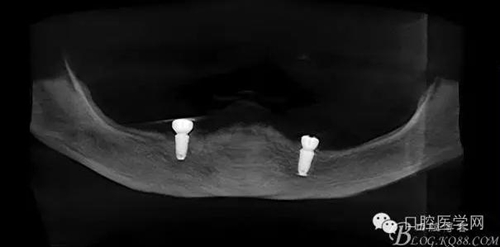

種植覆蓋全口義齒X線顯示骨量條件可以,準(zhǔn)備從下頜兩側(cè)大概3、4的位置植入植體。

種植覆蓋全口義齒判斷位置。

種植體植入后